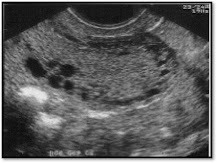

Patología Estructural